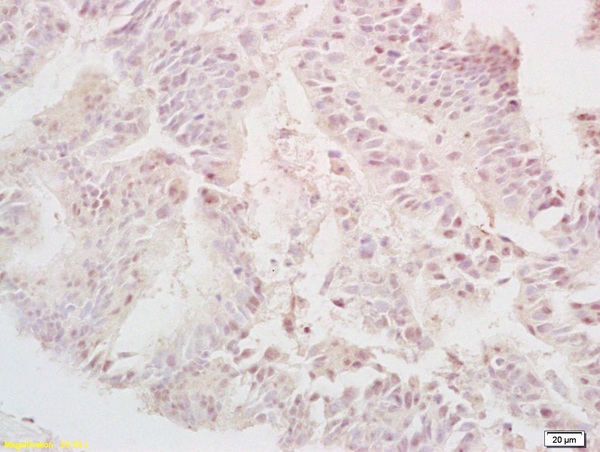

TGF alpha Polyclonal Antibody

Product Name TGF alpha Polyclonal Antibody

Background TGF alpha is a mitogenic polypeptide that is able to bind to the EGF receptor/EGFR and to act synergistically with TGF beta to promote anchorage-independent cell proliferation in soft agar.